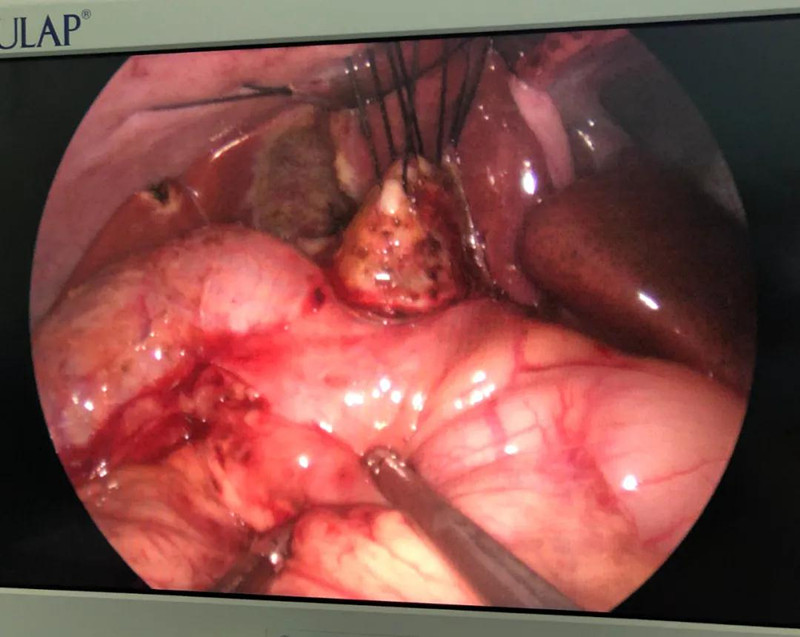

术前准备完毕。 9月25日,馨馨进入手术室。由崔钊主任带队,按照术前设计的方案,经过8个小时的奋战,手术成功了。馨馨肝总管以下病变的胆总管及胆囊全部切除,肝总管断面与肠管吻合接上,让胆汁直接流到肠腔里,帮助消化。如术后不出现胆瘘、肠瘘,没有梗阻,馨馨以后就可以正常生活了。目前馨馨恢复得很好,黄疸渐渐缓解,肝功正常,白细胞也降下来了,排气、排便都没问题,引尿管里也没有异常东西。

再谈及这台手术,崔钊主任说,其实当时手术的决定下得并不轻松,因为这台手术仅次于器官移植,相当于三、四项手术放一起来做。腹腔镜手术难度已经很大了,还是单孔,这也算是小儿普外科最尖端的微创手术了。